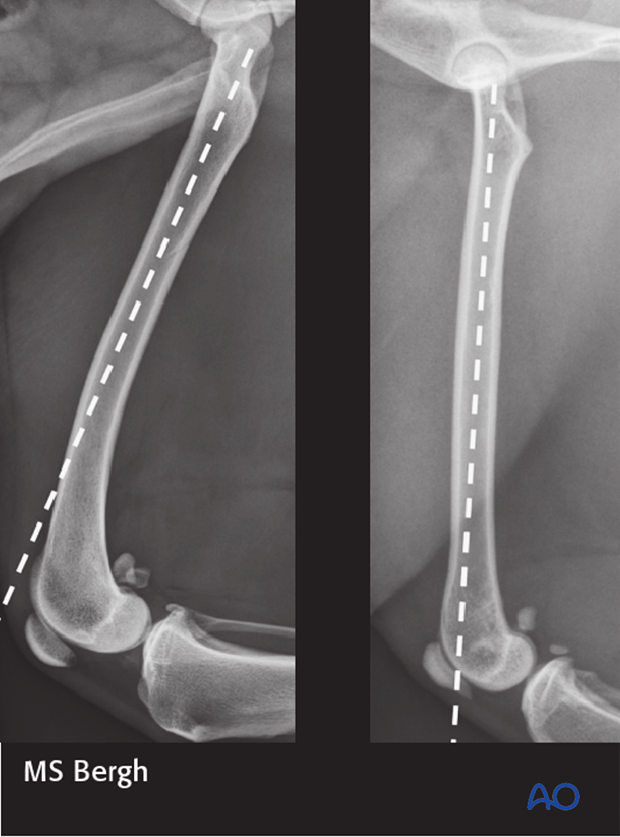

The diaphysis of the canine femur (left) typically has a cranial bowing to it, whereas the feline femur (right) is typically very straight.

The straightness of the feline femur makes it more amenable to modified Rush/dynamic intramedullary pinning technique of distal femoral fractures.